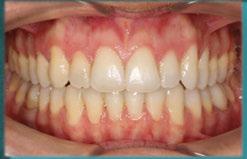

Figura 12. Comparativa de imágenes prequirúrgicas y seguimiento. a) situación clínica basal del quinto sextante. Vista frontal/vestibular. b) situación clínica del quinto sextante tras 36 meses de seguimiento. Vista frontal/vestibular. c) situación clínica basal del quinto sextante. Vista oclusal. d) situación clínica del quinto sextante tras 36 meses de seguimiento. Vista oclusal.

En un seguimiento a medio plazo, se puede observar un mantenimiento adecuado de los resultados en términos de salud periodontal, cobertura radicular, aumento de encía queratinizada y de profundidad de vestíbulo.